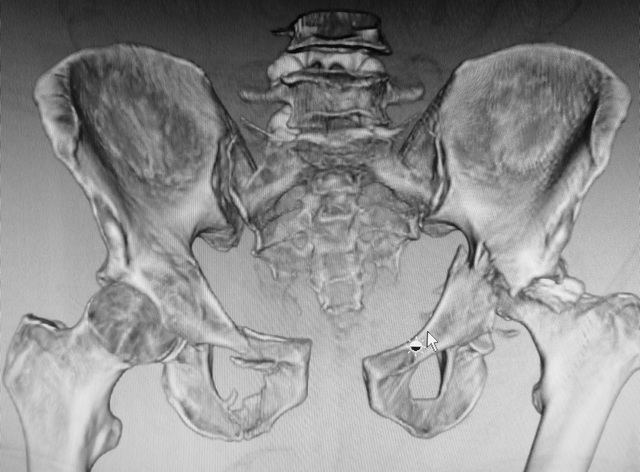

Мужчина 50 лет. Социальный, активный. Политравма 6 сут назад.

Со стороны живота - разрыв брыжейки, сейчас все ОК. Стабилен, в сознании, Hb 75. Таз на фото. Мой план: 1. IS справа, 2. поперечник и задняя стенка задним доступом, 3. передние отделы. Хотелось бы услышать ваше мнение, возможно рациональнее будет что-то другое?PS рентгена нет, был body scan